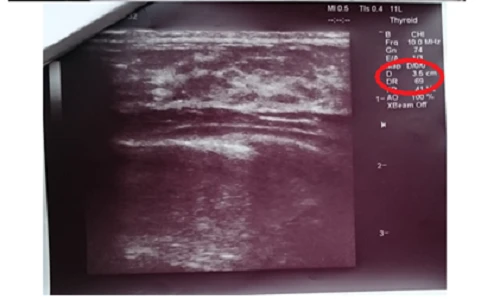

(Kiến Thức) - Sau 3 tháng sử dụng TPCN hỗ trợ điều trị u vú nhờ công thức chiết xuất từ thảo dược, khối u vú kích thước 3 cm của bệnh nhân đã giảm đi rõ rệt.